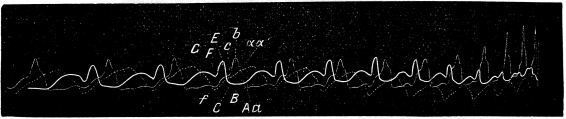

У больного было найдено увеличеніе размѣровъ сердца (правая граница сердца проходила на 2 сант. вправо отъ праваго края грудины, лѣвая граница заходила за 1. mamill. sin. на 2 1/2 сант., сердечный толчекъ соотвѣтственно былъ смѣщенъ влѣво за сосковую линію). При аускультаціи выслушивались очень рѣзкіе систолическіе шумы, какъ въ мѣстности сердечнаго толчка, такъ точно и внизу грудной кости; шумы эти отчетливо, хотя и слабѣе, слышны были въ аортѣ и легочной артеріи. Дѣятельность сердца была нѣсколько аритмична. Пульсъ art. radialis былъ хорошо ощутимъ. Вены на шеѣ представлялись набухшими и ясно пульсировали на глазъ и кромѣ того на нихъ передавались дыхательныя движенія. Въ легкихъ имѣлась масса разнообразныхъ хриповъ. Печень увеличена: прощупывалась. У больного имѣлся отекъ конечностей, одышка.

Разсматривая полученную флебограмму (см. фиг. 18-ю а и b), отличаемъ на ней двѣ волны: предсердіальную abc, рѣзко выраженую и желудочковую cfg, состоящую изъ двухъ подъемовъ: 1-го, во время періода напряженія и 2-го, значительно большаго во время періода изгнанія; второй изъ вихъ начинается ранѣе пульса art. radialis, т. е., другими словами, почти совпадаетъ съ пульсомъ art. carotidis. Большая величина предсердіальной волны и существованіе подъема на флебограммѣ во время 1-го періода систолы желудочка заставляютъ признать въ данномъ случаѣ, по сравненію съ предыдущими, меньшую недостаточность сердечной мышцы.

Фиг. 18a

Флебограмма этого 3-го случая вполнѣ напоминаетъ кривую веннаго пульса (см. фиг. 14), записанную отъ больной собаки, гдѣ недостаточность сердечной мышцы была не очень велика. Больныхъ животныхъ съ высокими степенями insufficientiae, выражающихся уменьшеніемъ предсердіальной и желудочковой волнъ во время періода напряженія какъ у людей, мнѣ не пришлось встрѣтить.

Я считаю невозможнымъ не описать еще одинъ, 4-й случай, изъ наблюдаемыхъ мною.

У больного, страдавшаго органической недостаточностью митральнаго клапана (систолическій шумъ у верхушки сердца и у основанія грудной кости, акцентъ 2-го тона легочной артеріи, смѣщеніе сердечнаго толчка влѣво за мамиллярную линію), констатировались ясно выраженныя пульсаціи яремной вены. Видъ ихъ кривой даетъ полную возможность рѣшить, происходитъ-ли шумъ у основанія грудины вслѣдствіе недостаточности valv. tricuspidalis, или-же онъ только проведенъ сюда отъ valv. mitralis.

На фиг. 19-й а и b изображена флебограмма этого больного. Оказалось, что на ней имѣется очень ясно выраженная волна aabc, возникающая нѣсколько раньше наступленія систолы предсердія, вслѣдствіе передачи пульсацій съ сосѣдней артеріи на вену, по оканчивающаяся точно къ началу систолы С желудочка. Это заставляетъ признать здѣсь нормальную флебограмму, а слѣдовательно, заключить, что недостаточности трехстворки нѣтъ и что слышимый шумъ зависитъ отъ insuff. mitralis и только проведенъ къ мѣсту выслушиванія трехстворчатаго клапана. Если здѣсь и существовало измѣненіе ѵ. tricuspidalis, то оно было настолько незначительно, что не нарушало функціи этого клапана. Пульсъ вены въ данномъ случаѣ, вслѣдствіе его ясности, можетъ быть названъ, по Potainy, акцентуированнымъ физіологическимъ.